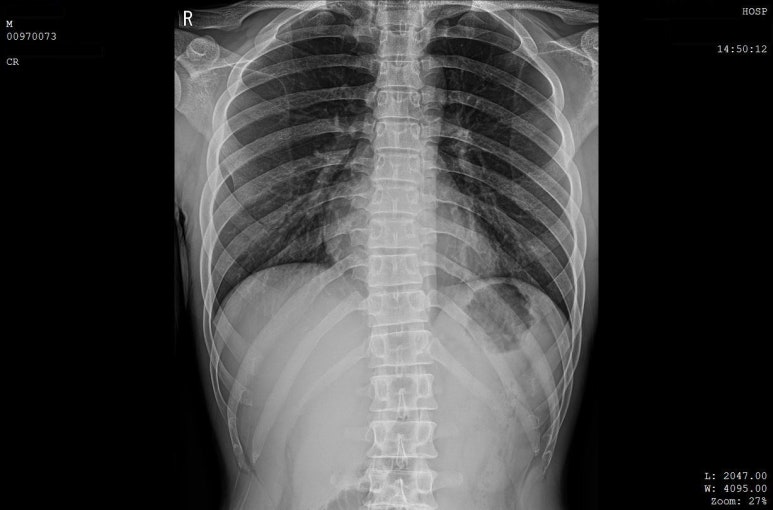

해당 환자분의 X-RAY 영상, 골절선이 보이지 않습니다.

병원에서 X-ray상

뼈는 멀쩡하다고 합니다.